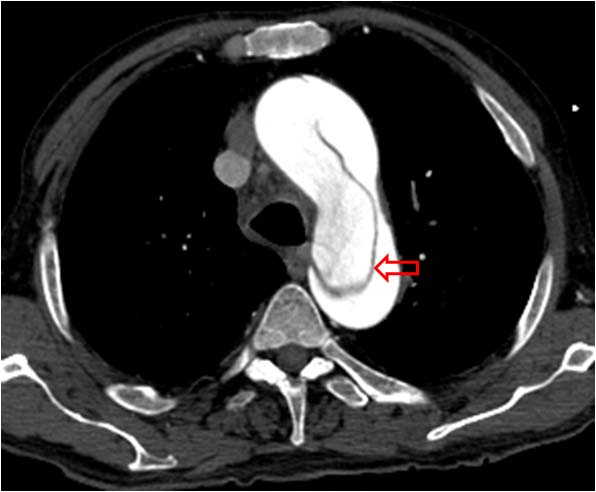

SIGNO DEL COLGAJO (O FLAP) INTIMAL

Signo de disección aórtica que puede verse tanto en ecografía, TC, resonancia magnética y arteriografía. Consiste en la presencia de una lámina -la capa íntima de la pared aórtica disecada- en el interior de la luz aórtica. En la imagen vemos un estudio de angioTC que muestra el colgajo tanto en la aorta ascendente como en la descendente. Puede distinguirse perfectamente la luz verdadera (más contrastada) de la falsa (menos densa).

Otro ejemplo del signo (flecha) en el que es más difícil diferenciar la luz verdadera de la falsa. A la izquierda del flap vemos una zona menos densa, es decir, se trata de la luz falsa.